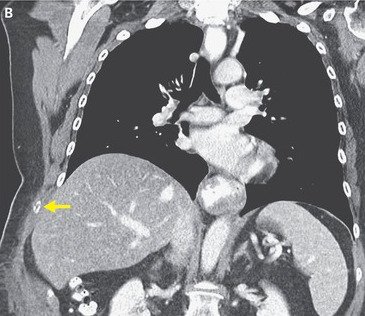

Η μελανιασμένη δεξιά πλευρά της 66χρονης οφειλόταν στο σπασμένο πλευρό. Φωτογραφία:New England Journal of Medicine

Η γυναίκα, από τη Μασαχουσέτη, υποβλήθηκε σε αξονική τομογραφία, η οποία αποκάλυψε ότι είχε μετατοπισμένο κάταγμα του 9ου πλευρού της – το πλευρό είχε σπάσει και τα δύο κομμάτια είχαν διαχωριστεί.